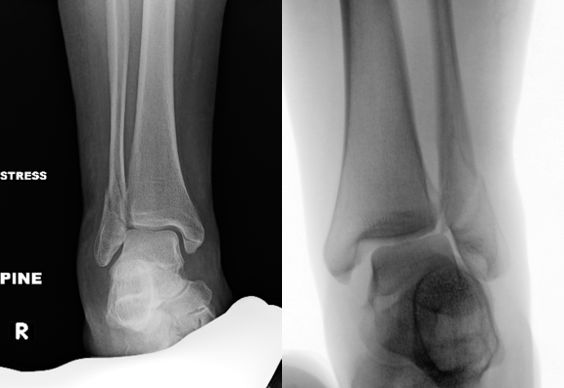

Stress Radiographs. Gravity or external rotation stress radiographs traditionally assess deltoid ligament integrity, particularly in isolated Weber B fractures. However, multiple studies demonstrate stress radiographs may overestimate instability, which may identify partial deltoid injuries that do not translate into functional ankle instability (Figure 2).3-5

Weight-Bearing Radiographs. More recent literature supports weight-bearing radiographs as a reliable and clinically relevant method to assess functional stability in select ankle fractures, particularly isolated Weber B injuries. Prospective studies show that patients with stable weight-bearing mortise alignment experience excellent outcomes with nonoperative treatment, even when stress views suggest instability.4-8 Although, a recent study by Zonneveld and Hoogendoorn in 2024 found substantial variability in the amount of weight-bearing on an ankle during weight-bearing radiographs, and to keep this information in mind when determining a treatment course.9